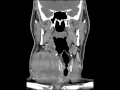

Anaplastic Thyroid Cancer

These images show a large heterogeneously enhancing mass which appears to originate from the right thyroid lobe with areas of central hypodensity likely reflecting necrosis. The mass extends from the level of the hyoid to the upper mediastinum, invades the right neck anterior strap musculature, results in significant leftward deviation of the trachea, and markedly compresses the right internal jugular vein. There is no cervical lymphadenopathy or evidence of osseous or cartilage invasion. The differential diagnosis includes anaplastic thyroid cancer, thyroid medullary carcinoma, and multinodular goiter. The presence of muscular invasion and necrosis in an older male makes anaplastic thyroid cancer the most likely diagnosis. This was confirmed on pathology. Anaplastic thyroid cancer is very aggressive tumor with a poor prognosis and mean survival of six months. Treatment is usually palliative, but if caught early, aggressive treatment may be pursued with surgery and/or chemoradiotherapy.